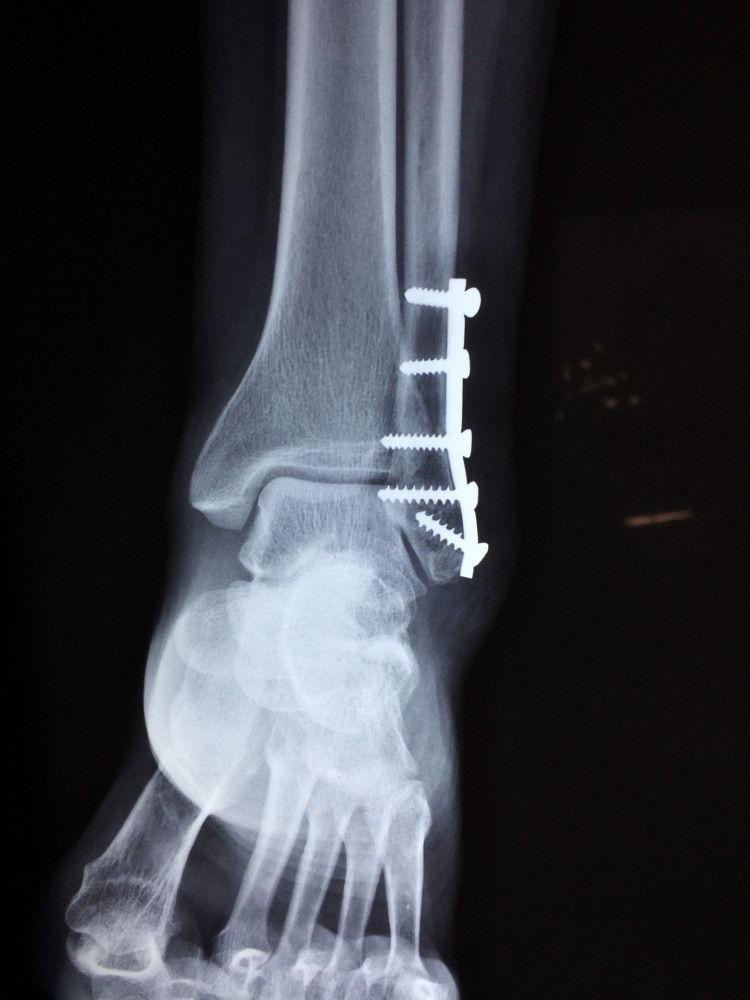

Nopietnas traumas cilvēki guvuši, paslīdot un krītot uz slidenām ielām. Visbiežāk gūtas roku, kāju, galvas un muguras traumas. Cietušie ir dažāda vecuma.